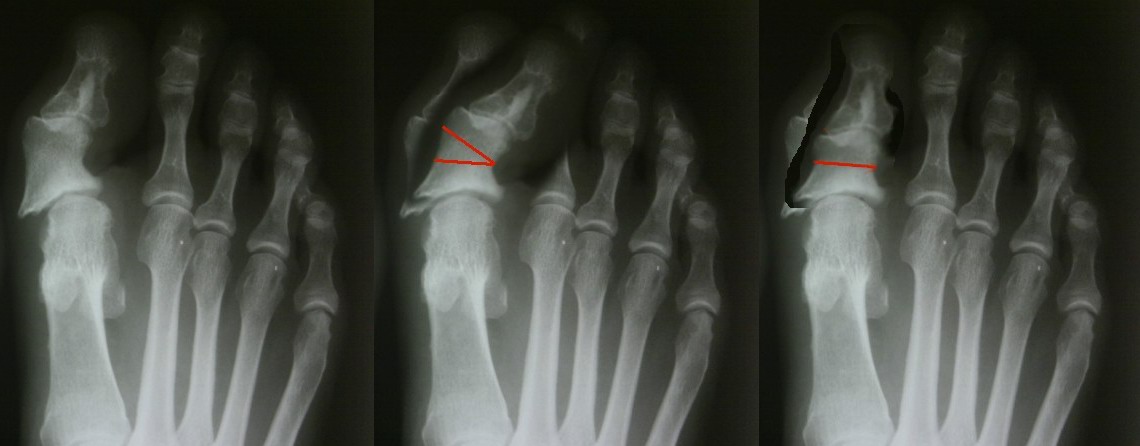

[Ortho] Неудачный результат

> Что можно предложить?

Если оперировать в фотошопе, то в принципе можно предложить е

Имя     : St.jpg